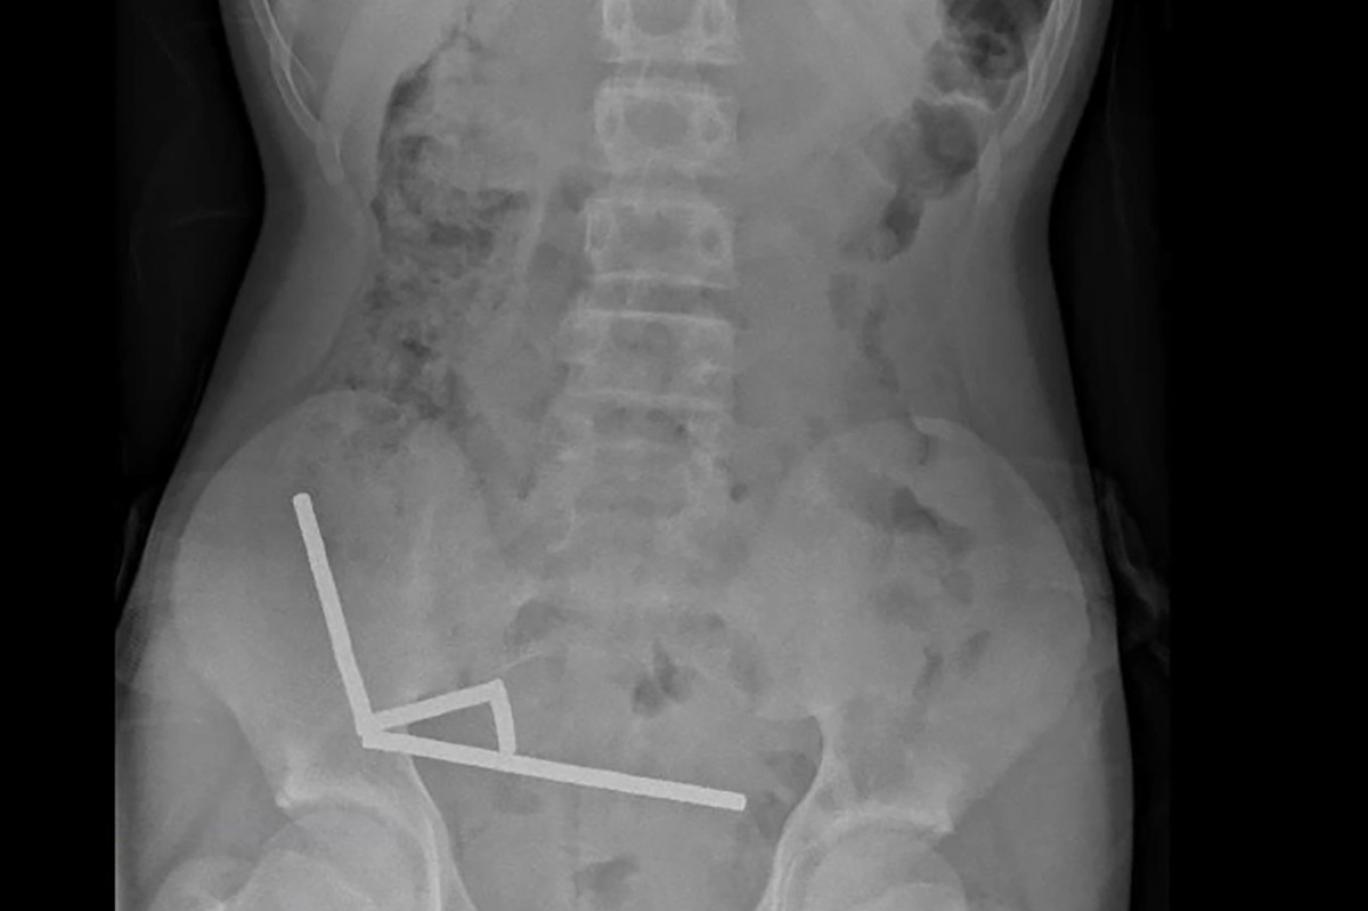

نیوزی لینڈ میڈیکل جرنل کی جانب سے 24 اکتوبر 2025 کو جاری کی گئی ایکس رے کی تصویر میں نیوزی لینڈ کے شہر ٹاورانگا کے رہائشی لڑکے کی آنتوں میں طاقتور مقناطیس کے ٹکڑے نظر آ رہے ہیں (اے ایف پی)

یہ مقناطیس نیوزی لینڈ میں جنوری 2013 سے ممنوع ہیں لیکن یہ ٹیمو سے خریدے گئے۔ ایکس رے میں دیکھا گیا کہ یہ مقناطیس لڑکے کی آنتوں میں چار سیدھی قطاروں میں جڑ گئے تھے۔

میڈیکل رپورٹ کے مطابق: ’یہ آنتوں کے مختلف حصوں میں تھے جو مقناطیسی قوت کی وجہ سے آپس میں چپک گئے۔‘